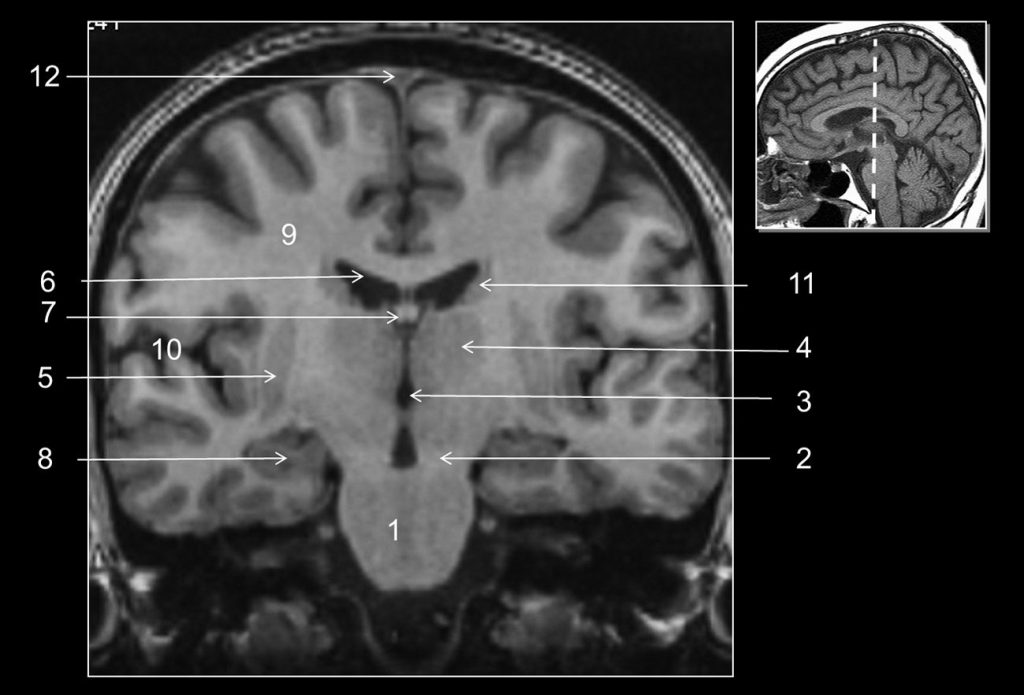

Fig. 48.9 Coupe frontale (coronale) (IRM en pondération T1).

1. Pont. 2. Pédoncule cérébral. 3. Troisième ventricule. 4. Thalamus. 5. Noyau lenticulaire. 6. Ventricule latéral. 7. Fornix. 8. Hippocampe. 9. Corona radiata. 10. Sillon latéral (de Sylvius). 11. Noyau caudé. 12. Sinus sagittal supérieur.

Source : CERF, CNEBMN, 2022.